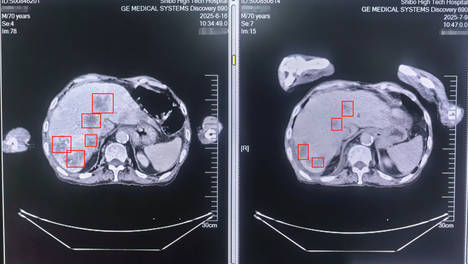

淄博世博高新医院:七旬肠癌肝转移患者的 “破局之战”

在“晚期肿瘤”与“拒绝手术”的双重挑战下,淄博世博高新医院肿😴瘤科团队没有放弃,而是以“个性化保守治疗”为突破口,为生命开😜辟了一条希望之路。晚期肿瘤≠放弃,根据病情和患者意愿定制的保🤗守方案,同样能控癌、延命、保…